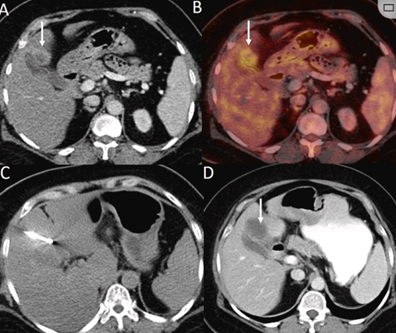

膽囊附近轉(zhuǎn)移灶(來自子宮頸癌)的冷凍消融術(shù)(A)門靜脈期 CT 圖像顯示膽囊附近有病變(箭頭)。(C) 手術(shù)過程中CT 顯示冷凍探針位于病灶內(nèi)。(D)消融手術(shù)后 1 個(gè)月CT 顯示完全消融。

CT引導(dǎo)的冷凍消融

(a) 射頻消融后在病變邊緣顯示殘余增強(qiáng)。(b) 冷凍消融術(shù)中影像顯示冰球完全覆蓋病變。(c) 19個(gè)月后隨訪,沒有發(fā)生局部腫瘤進(jìn)展。完全消融率為97%(66/68);2名患者均接受了額外的冷凍消融,隨后實(shí)現(xiàn)完全消融。平均隨訪期為 12.8 個(gè)月(范圍:3-27 個(gè)月)。所有患者均接受影像復(fù)查(CT 或 MRI)。11個(gè)病灶(16.2%)檢測到局部腫瘤進(jìn)展,6、12和18個(gè)月時(shí)的累積局部腫瘤進(jìn)展率分別為4%、8.2%和20.5%。8例出現(xiàn)遠(yuǎn)處肝內(nèi)或肝外病變的患者接受經(jīng)動脈化療栓塞、經(jīng)動脈化療栓塞加射頻消融治療或全身化療。